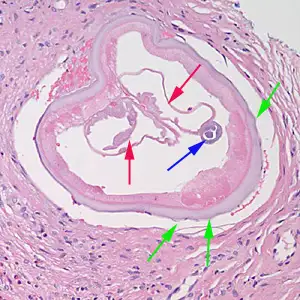

当感染性幼虫进入人体皮肤后,它们会在数月内发育成熟。雄虫相对较小,体长约2至4厘米,细如发丝;而雌虫则可达30至50厘米长,直径约0.3至0.4毫米,是名副其实的"巨虫"。成虫并不四处游荡,它们将自己蜷曲成团,深埋在皮下结缔组织中,形成特征性的纤维结节——医学上称为"盘尾丝虫结节"或"蟠尾蚴瘤"。

这些结节通常出现在骨性突起部位附近,如髋部、肋骨、肩胛骨和头颅。结节大小不一,从豌豆大小到高尔夫球大小不等,触感坚硬,通常无痛。一个感染者体内可能只有一两个结节,也可能多达数十个。在严重感染的病例中,结节几乎可以出现在身体的任何部位,包括头部和眼部周围。

在眼前段,微丝蚴主要影响角膜。当它们在角膜基质中死亡时,会释放包括沃尔巴克氏体细菌在内的抗原物质,触发一系列复杂的免疫反应。人体派出嗜酸性粒细胞和中性粒细胞等炎症细胞围剿这些死亡的幼虫,而这些细胞释放的毒性物质,包括主要碱性蛋白、嗜酸性粒细胞阳离子蛋白和嗜酸性粒细胞过氧化物酶,对角膜细胞具有直接的细胞毒性作用。

随着病情进展,角膜边缘开始出现新生血管——这是一种绝望的修复尝试,却反而加速了角膜的破坏。血管从角膜缘长入,伴随着纤维组织的增生,角膜逐渐变得混浊、不透明。这种被称为硬化性角膜炎的病变,最终会覆盖整个角膜,使光线无法进入眼内,导致不可逆的失明。

沃尔巴克氏体细菌在河盲症的发病机制中扮演着关键角色。这种细胞内共生菌存在于盘尾丝虫的所有生命阶段,对成虫的生存和繁殖至关重要。当微丝蚴在角膜中死亡时,沃尔巴克氏体被释放出来,其表面蛋白是强效的炎症触发因子。研究表明,针对沃尔巴克氏体的免疫反应是角膜损伤的主要驱动因素。